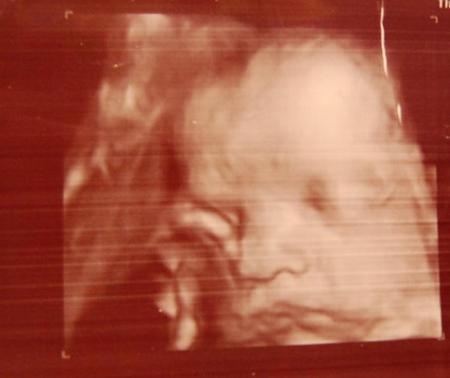

hier ein bild vom 22.12.2010

ui, so süße bilder... ja, das mit dem größer sein kenne ich auch. dieses baby ja bislang gsd noch nciht... und die symphysenschmerzen. reich mir die Hand, aber naja, sobald das baby draußen ist, sind sie ja shcon besser....^^

Tolle Bilder!!! Mein Bauchzwerg dreht sich immer vor dem US-Gerät ab, sodass wir zuletzt (auch am 22.12!) keine richtige Bilder bekommen konnten. LG